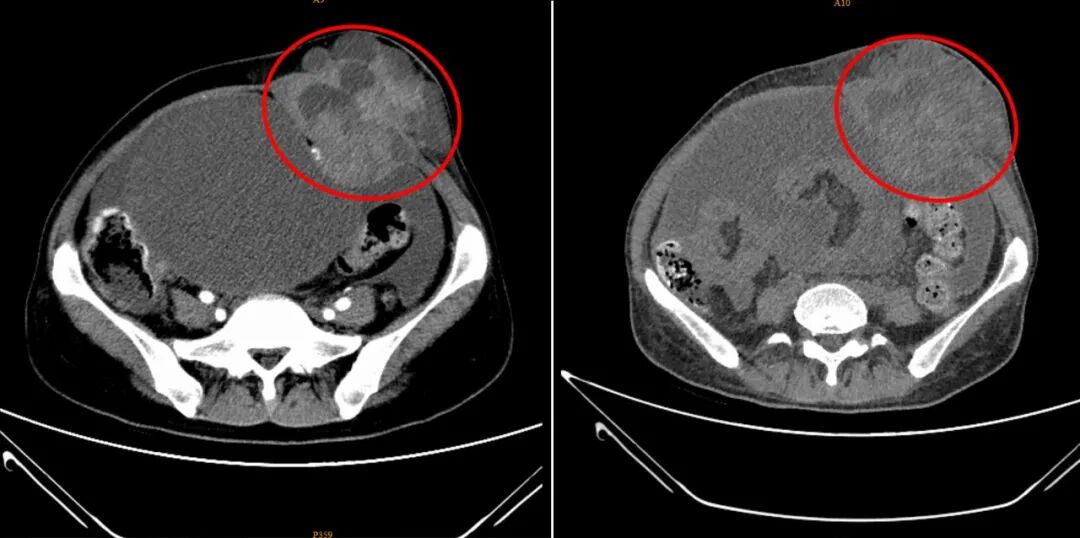

孙女士在深圳华侨医院治疗短短一个月的前后对比CT影像图。病灶部位呈现出体积显著缩小、边界趋于清晰、内部密度更加均匀的积极变化,表明治疗已取得明显成效。

在深圳华侨医院的精准微创治疗下,孙女士的身体状况发生了翻天覆地的变化,这份变化,不仅体现在检查报告上,更体现在她实实在在的身体感受中。接受冷冻消融术后不久,她就发现腹部的肿瘤肿块有了明显缩小,“用手摸能感觉到小些,从外观都能看出来,比之前拍片子的时候小了不少。” 而最让她欣喜的是,困扰她许久的睡眠问题彻底解决了,曾经两三个月彻夜难眠、只能趴着休息的她,如今能像正常人一样平躺、侧睡,“枕着一个枕头就能睡好觉,这种轻松的感觉太久没有了,我现在晚上睡觉特别香。”